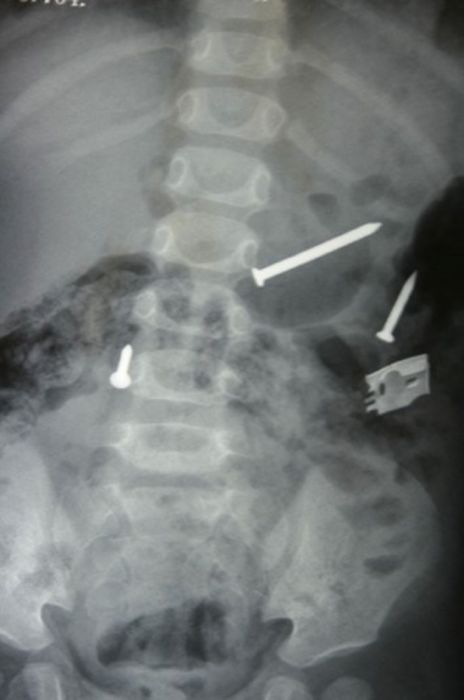

Жуткие рентгеновские снимки

Порой даже не верится, с какими странными и необычными повреждениями в травматологию могут поступить пострадавшие. Всю эпичность профессии врачей травматологии могут с легкостью подтвердить рентгеновские снимки. Просто жесть, да и только..